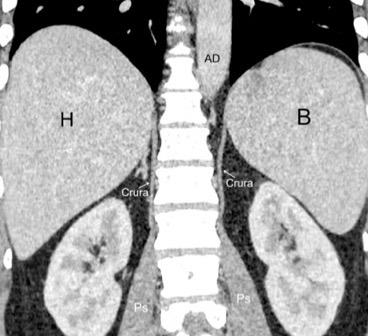

Parte lumbar: 1.Ligamentos arcuatos medial y lateral

2. Cruras conectadas a vértebras lumbares y discos. L1-3 a la dcha. L1-2 a la izda.

Cruras conectadas por encima del tronco celíaco por ligamento fibroso arcuato medial. Panicek DM et al. Radiographics. 1998

Las fibras más bajas de las cruras se funden con las de las vainas de los músculos psoas, acotando un espacio llamado “Espacio abierto de la vaina del psoas”, que comunica las cavidades torácica y abdominal.

Panda A et al. “Straddling Across Boundaries”. Thoracoabdominal Lesions: Spectrum and Pattern Approach. Curr Probl Diagn Radiol, 2015 /Restrepo CS et al. The diaphragmatic crura and retrocrural space: normal imaging appearance, variants, and pathologic conditions. Radiographics 2008